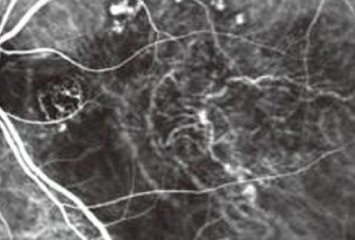

蛍光眼底造影検査(けいこうがんていぞうえいけんさ)

蛍光色素を腕の静脈に注射し、眼底カメラで眼底の血管の異常を検査します。フルオレセイン蛍光眼底造影(FA)とインドシアニングリーン蛍光眼底造影(IA)があります。

• 加齢黄斑変性のFA

• 加齢黄斑変性のIA